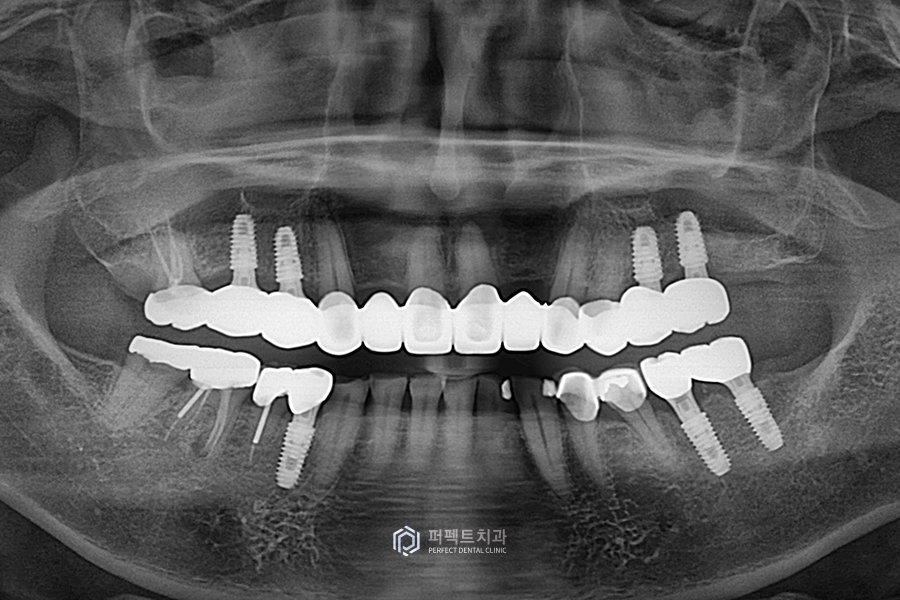

이렇게 어금니는 총 7개의 임플란트를 식립했고, 앞니 보철과 아랫니 부분도 꼭 해야하는 부분은 다시 재치료를 했습니다.

없는 치아들은 임플란트를 통해 수복을 했고 위, 아래 사랑니도 발치를 하였습니다. 그리고 마찬가지로 앞니 부분 옛날 보철들을 지르코니아 크라운으로 교체를 했습니다.

상악 사진을 보시면 뿌리만 남은 치아들과 치아가 없는 부분들을 임플란트로 수복하고, 앞니 보철까지 교체를 해서 윗니 전악 보철 케이스가 된 경우입니다.

아랫니 같은 경우도 뿌리만 남은 부분들을 임플란트를 통해 수복을 했고, 자연치아는 쓸 수 있는 경우여서 치료를 하지 않고 그대로 사용하고 있는 경우입니다.

치아가 없는 부분은 임플란트로, 기존 보철물은 지르코니아 크라운으로 교체를 해서 윗니는 전체적으로 치아가 다시 완성된 케이스라고 생각을 하시면 될 것 같습니다.